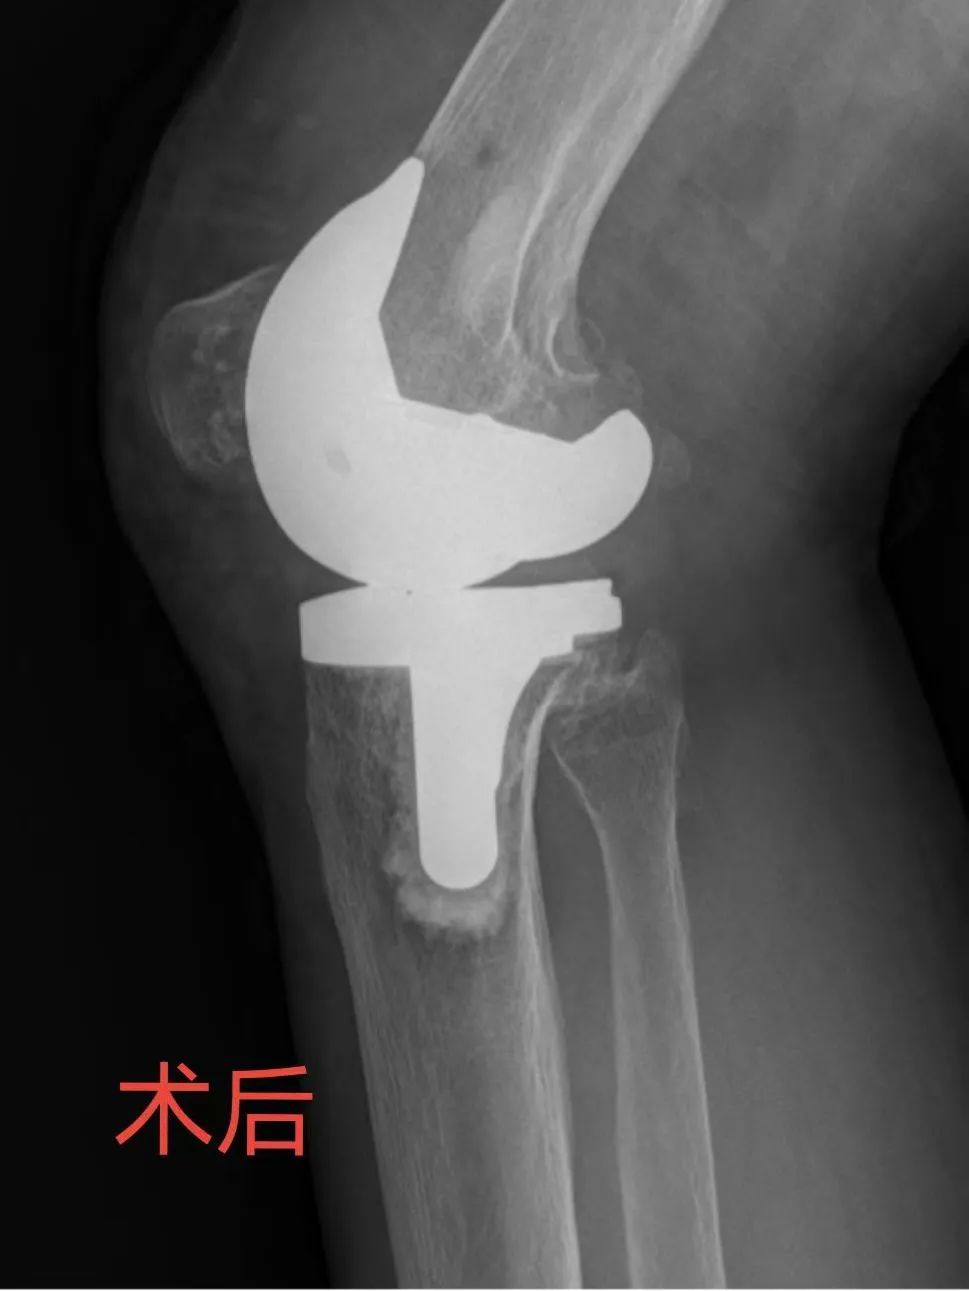

▲左側(cè)為術(shù)前X片,右側(cè)為術(shù)后X片